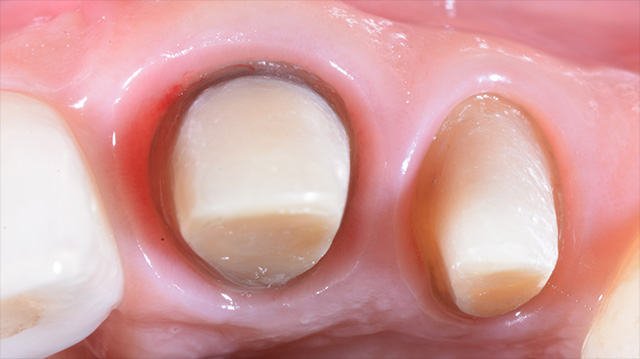

| 年代・性別 | 40代 女性 |

|---|---|

| 主訴 | 前歯の見た目をどうにかしたい |

| 治療回数 | 3回 |

| 治療期間 | 約1ヶ月 |

| 費用 | 歯茎の移植 70,000円 / 1本 |

*キャンセルポリシーをご一読のうえご予約ください